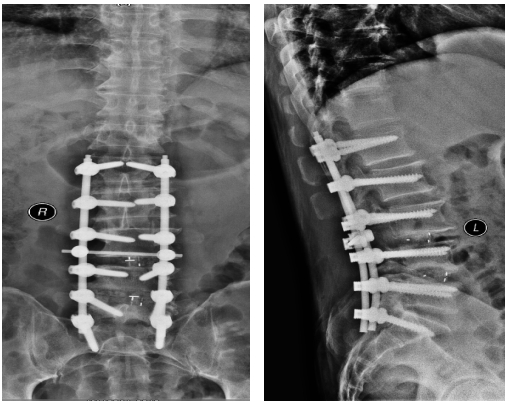

术后影像

天时地利人和,一切准备就绪,2019年1月7日,骨一科对王师傅成功实施了“经后路腰椎侧弯畸形矫形+钉棒螺钉内固定+腰3/4、4/5椎管切开减压+腰4/5 、骶1双侧神经根探查松解+椎间盘切除+椎间、椎体后侧植骨融合术”,手术历时5小时45分。术后患者恢复良好,腰部侧弯、腰痛等问题一去不复返。